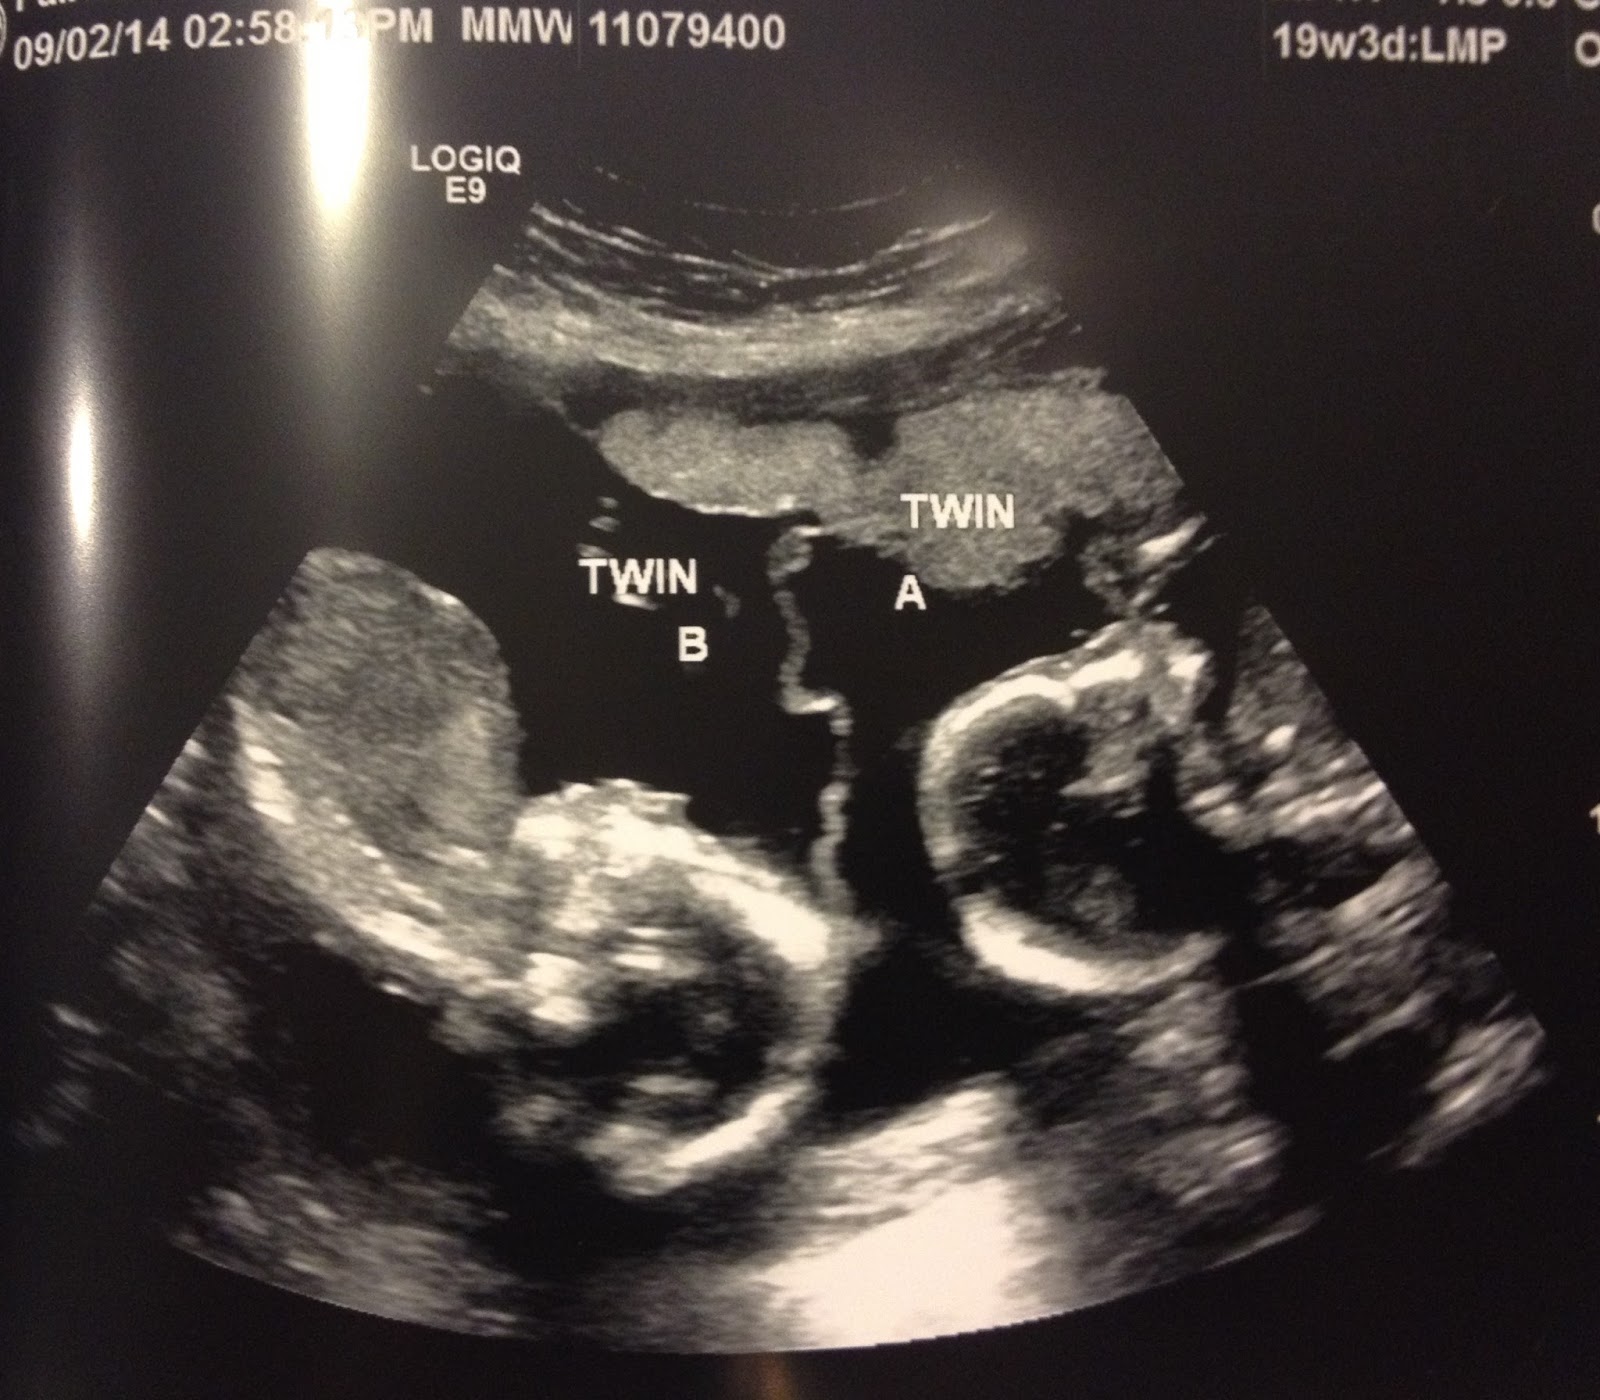

My Mono Mono Twin Girls At 19 Week Ultrasound

19 Weeks Ultrasound 19wks Twiniversity